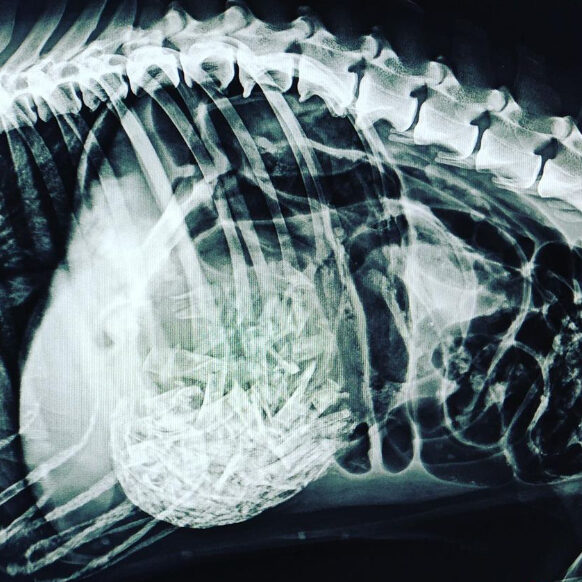

El Dick va venir d’urgències perquè no el veien bé. Tenia molt dolor abdominal i li vam fer una radiografia. En aquest cas, la imatge ens va donar un diagnòstic! Li vam diagnosticar una torsió d’estòmac degut a la ingesta d’ossos de pollastre. L’única manera per poder-li salvar la vida al Dick era sotmetre’l a…